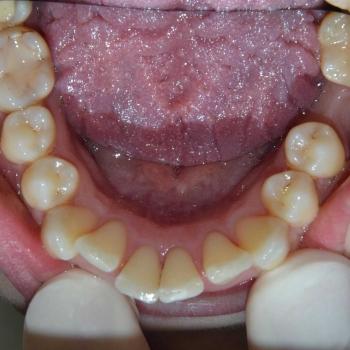

Tünde a felső fogív torlódása, illetve az alsó metszőfogak között található rések miatt keresett fel. Az első találkozásunk alkalmával azonban fény derült a középvonalak eltolódására, enyhe mélyharapásra, a felső metszőfogak túlzott elülső pozíciójára, illetve a régóta hiányzó alsó 6-os fog helyének beszűkülésére is, így a kezelési terv ezen problémák megoldására is kitért.

Tünde végül úgy döntött, hogy nem csak az esztétikai, de a funkciós problémák is szeretné megoldani, melyhez hagyományos fém fogszabályozót választott. A fogszabályozáshoz különböző kiegészítőket is igénybe vettünk úgy, mint harapásemelő, különböző intermaxillaris gumihúzások, illetve egy speciális szájpadi mini-implantátum a hozzá kapcsolódó transpalatinalis ívvel (hibrid transpalatinal ív), ami minimalizálta a hátsó fogak mozgását, miközben a felső metszőfogak hátrafele mozogtak.

A kezelés végére minden problémát sikerült megoldanunk, a középvonalak korrekcióját leszámítva. Ennek ellenére, mivel a felső középvonal az arc tengelyében helyezkedik el, az esztétikai eredmény nem csorbult és a funkciót sem befolyásolta. A jobb alsó 6-os fog implantációs pótlása a fogszabályozás befejeztével kezdődött meg.